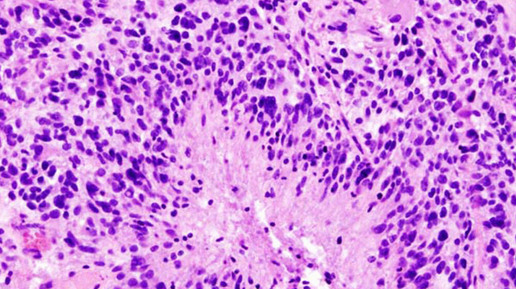

Ученые разгадали секрет агрессивности глиобластомы

Американские онкологи выяснили, почему глиобластома остается одной из самых агрессивных и неподдающихся лечению форм рака. Эксперименты на мышах показали, что опухоль разрушает череп и костный мозг внутри него, что делает саму опухоль еще более агрессивной, говорится в работе, опубликованной в журнале Nature Neuroscience. Глиобластома — наиболее агрессивная из известных форм опухоли мозга. Глиобластомы часто растут в лобной и височной долях мозга, также они могут быть обнаружены в стволе мозга, мозжечке, других частях головного и спинного мозга...